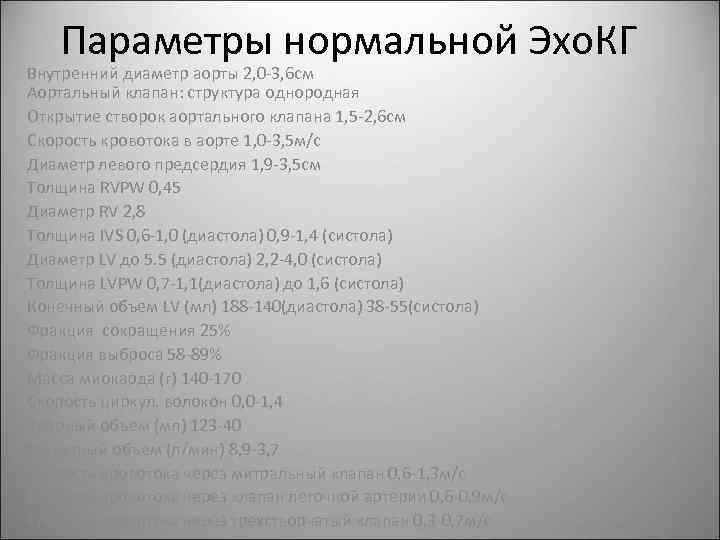

Нормальный диаметр корня аорты: медицинские нормы и отклонения